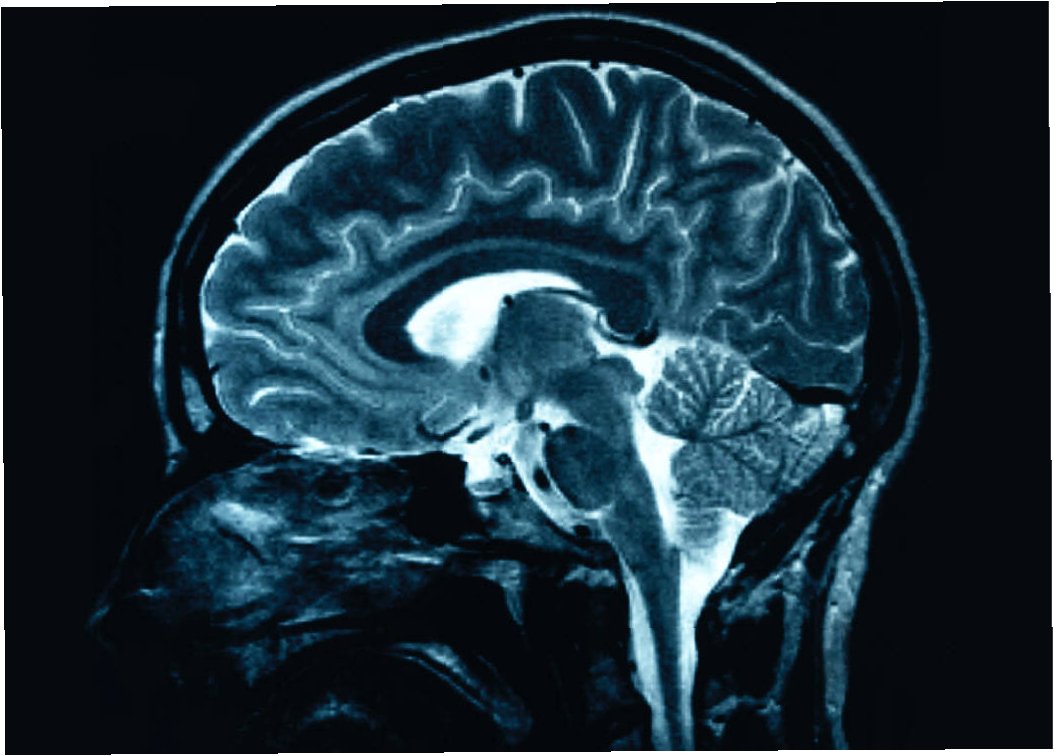

뇌전증은 정확한 진단을 통해 적절한 치료 계획을 수립하는 것이 중요합니다. 뇌전증 진단에는 환자의 병력 청취와 신경학적 검사, 뇌파 검사(EEG), 뇌 MRI 등의 검사가 활용됩니다. 뇌파 검사는 뇌의 전기적 활동을 기록하여 발작의 원인을 파악하는 데 도움을 주며, 뇌 MRI는 뇌의 구조적 이상을 확인하는 데 사용됩니다. 뇌전증의 치료는 약물 치료가 기본이며, 발작의 종류와 빈도, 환자의 상태 등을 고려하여 적절한 약물을 선택합니다. 약물 치료 외에도, 약물 치료에 반응하지 않는 환자에게는 수술적 치료나 미주 신경 자극술과 같은 다른 치료법을 고려할 수 있습니다. 뇌전증 치료는 장기간에 걸쳐 이루어지는 경우가 많으며, 꾸준한 치료와 관리가 필요합니다. 뇌전증 환자는 정기적인 진료를 통해 질병의 경과를 관찰하고, 부작용을 관리하며, 필요에 따라 치료법을 변경해야 합니다.